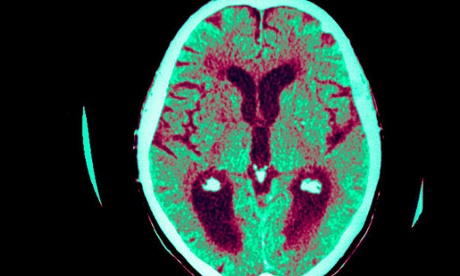

Alzheimer's disease brain scan

Brain scan of a person with Alzheimer’s disease. Researchers have found two licensed drugs which halt brain degeneration in mice. Photograph: Alamy